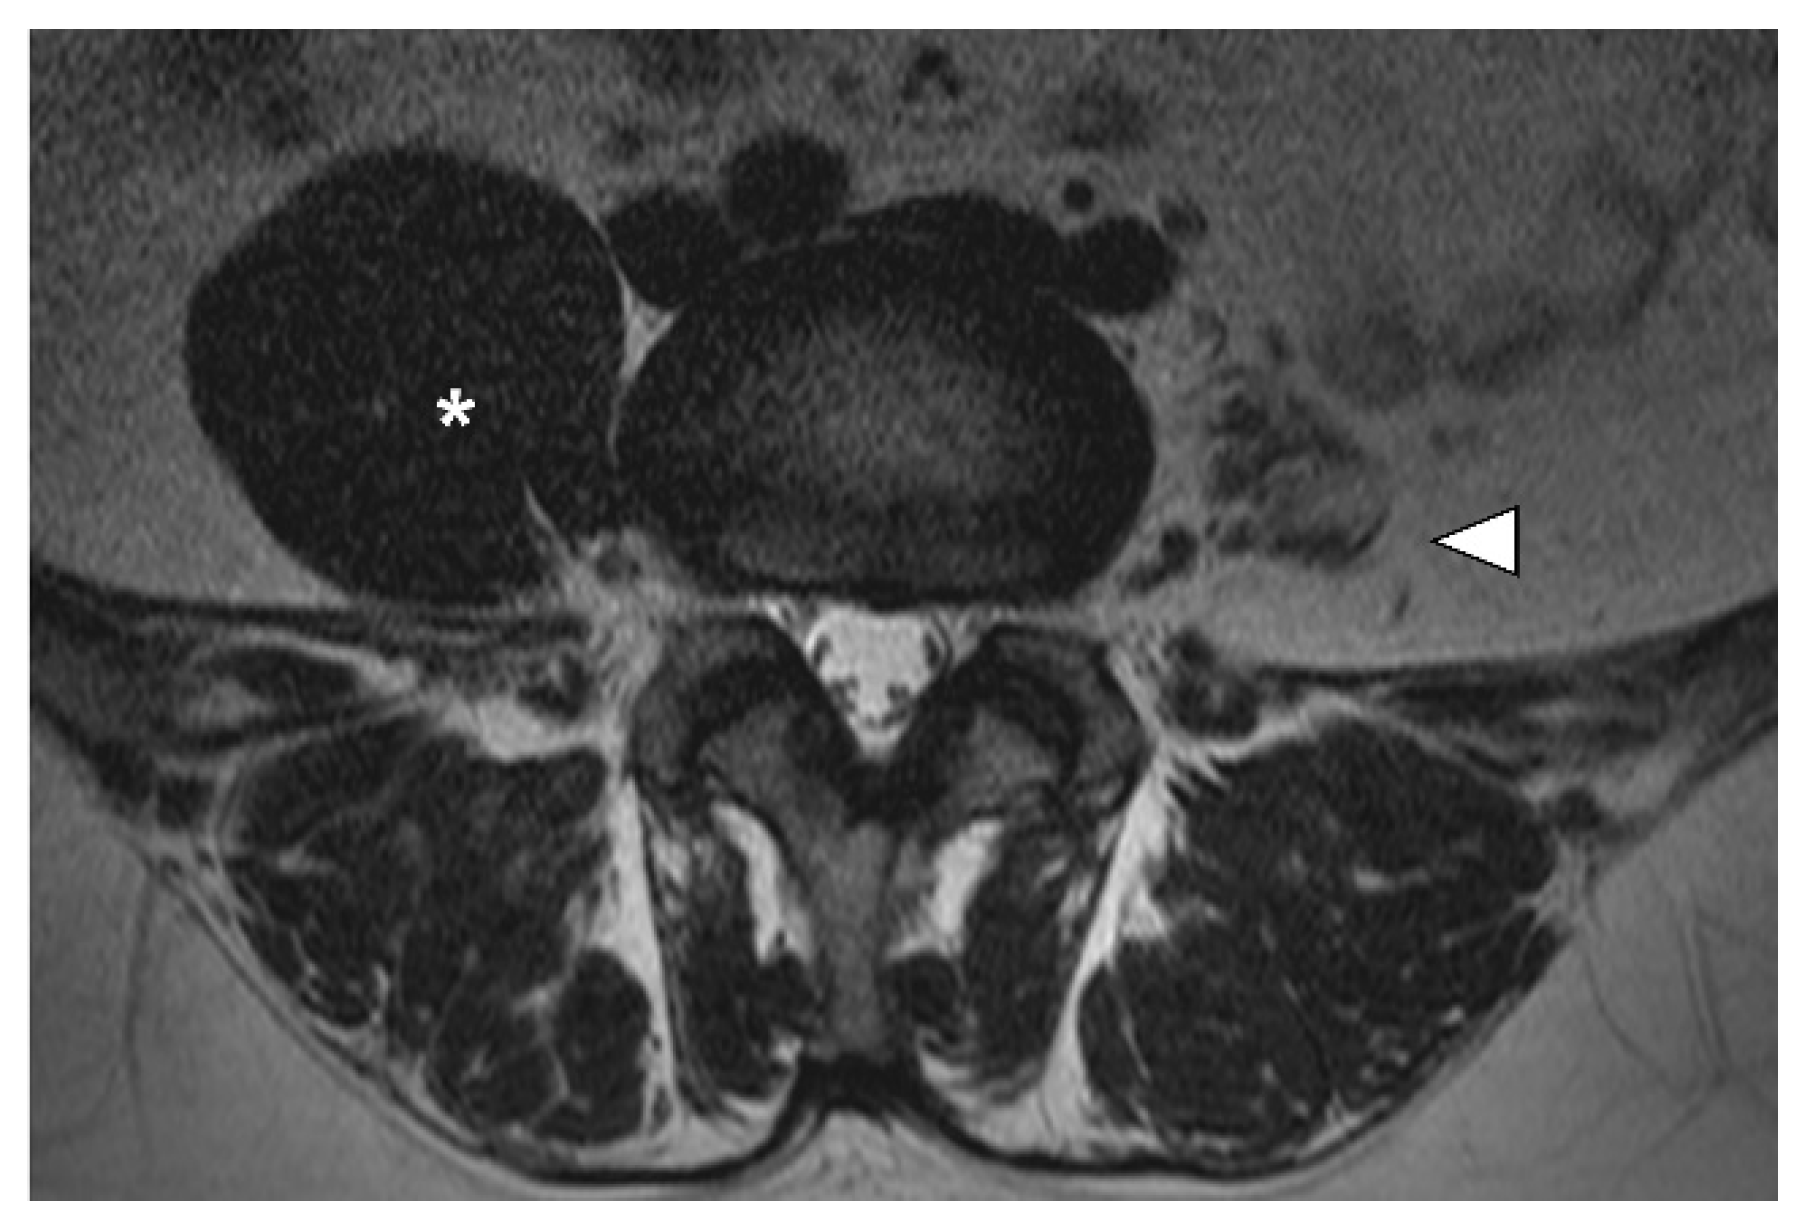

2. Case Presentation